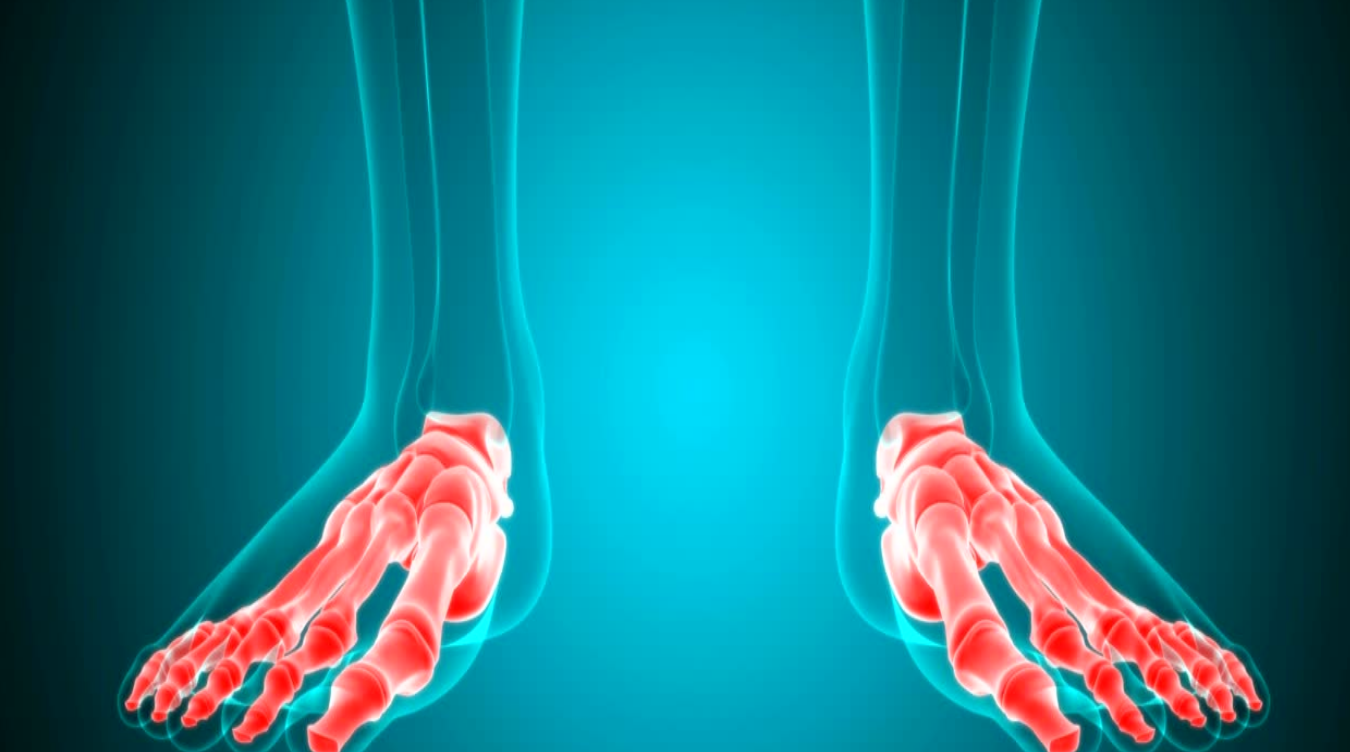

By continuous overexertion an inflammation can occur at the insertion of the tendon: fasciitis plantaris. This tendon takes care of the medial foot arch.

As with many inflammations, swelling and pain will exist (especially in the morning!), and you will walk differently. This process is reversible, but the cause remains: the falling arch.